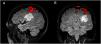

AimsThis work aims to assess the usefulness of functional magnetic resonance imaging (fMRI) in the preoperative study in four patients with DNET. A Philips Intera 3.0 Tesla magnetic resonance imaging scanner and the Blood-Oxygen-Level-Dependent (BOLD) technique were used to obtain the images, making it possible to locate the eloquent areas for language and motor areas through the application of specific paradigms.

ResultsIn one case the tumour was adjacent to Broca’s area, in two cases it coincided with Wernicke’s area, in one patient it was <1 cm from the motor area for the hand and in another close to memory. Only two of the patients were operated on, without postoperative functional deficit. Hemispheric activation contralateral to the tumour suggestive of neuroplasticity was observed in one of the patients.

ConclusionsfMRI is a non-invasive method that allows us to assess the proximity of lesions to eloquent areas, which is key in the evaluation of surgical risk. In addition, it allowed the detection of probable neuroplasticity in one case, which guaranteed the success of the surgery